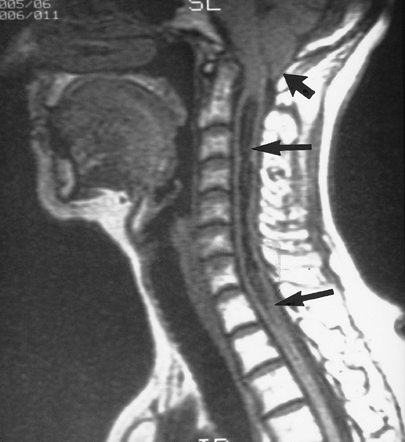

Congenital Anomalies: Chiari Malformation

-

Type I: Adult type. Inferior displacement

of cerebellar tonsils and sometimes the inferior vermis through the

foramen magnum. Syringomyelia may occur because of cerebrospinal fluid

flow obstruction. (By convention, tonsillar ectopia should be more than

5 mm inferior to a line drawn from the basion to the opisthion.)

Associated with Klippel-Feil anomalies. -

Type II: Also known as Arnold-Chiari

malformation childhood. Posterior fossa is small, with displacement of

tonsils, medulla, and vermis through an enlarged foramen magnum. The

cervicomedullary junction may appear kinked. Meningocele or

meningomyelocele and hydrocephalus are nearly always associated. -

Type III: More severe. Displacement of entire cerebellum into upper cervical or occipital encephalocele.

![]() |

|

FIGURE 3-72 Type I Chiari malformation. Sagittal T1-weighted MR image showing the cerebellar tonsils below the foramen magnum (short black arrow) with a large syrinx (double arrows). (From

Witte RJ, Miler GM. Spine. In: Berquist TH, ed. MRI of the musculoskeletal system. 4th ed. Philadelphia: Lippincott Williams & Wilkins; 2001:103–194.

) |